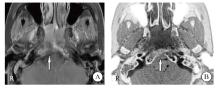

Background and purpose: Owing to the reliance on computed tomography (CT) for evaluating skull-base bone invasion in nasopharyngeal carcinoma and the potential harm of ionizing radiation from CT, zero echo time magnetic resonance imaging (ZTE-MRI) offers high-resolution bone delineation without radiation exposure. Therefore, this study aimed to systematically assess the diagnostic performance of ZTE-MRI for detecting skull-base bone invasion and to explore its clinical feasibility as an alternative to CT. Methods: This prospective study collected 95 nasopharyngeal carcinoma patients treated in Fujian Provincial Cancer Hospital from April 2020 to December 2022 as the research subjects. The patients who do not meet the inclusion standards would be excluded. Using the GE Discovery 750W 3.0T MR scanner to obtain unenhanced scan and enhanced scan, using ZTE-MRI technology to obtain ZTE-MRI and CT image. The results of the imaging scans were used to independently assess skull base bone invasion by two radiologists. This study was approved by the Ethics Committee of Fujian Cancer Hospital (K2025-314-01), and informed consent from the patients were obtained. Results: A total of 80 nasopharyngeal carcinoma patients were included in the final analysis. There was a high degree of consistency between CT diagnosis of nasopharyngeal carcinoma skull base bone invasion and of gold standards, and the difference was statistically significant (κ=0.645, P<0.001). There was a high degree of consistency between ZTE-MRI diagnosis of nasopharyngeal carcinoma skull base bone invasion and of gold standards, and the difference was statistically significant (κ=0.774, P<0.001). There was a high degree of consistency between ZTE-MRI combined with conventional MRI diagnosis of nasopharyngeal carcinoma skull base bone invasion and gold standards, and the difference was statistically significant (κ=0.912, P<0.001). Conclusion: ZTE-MRI technology provides "like CT" images for the skull base bone invasion in nasopharyngeal carcinoma, and ZTE-MRI technology can replace CT examination in clinical practice.